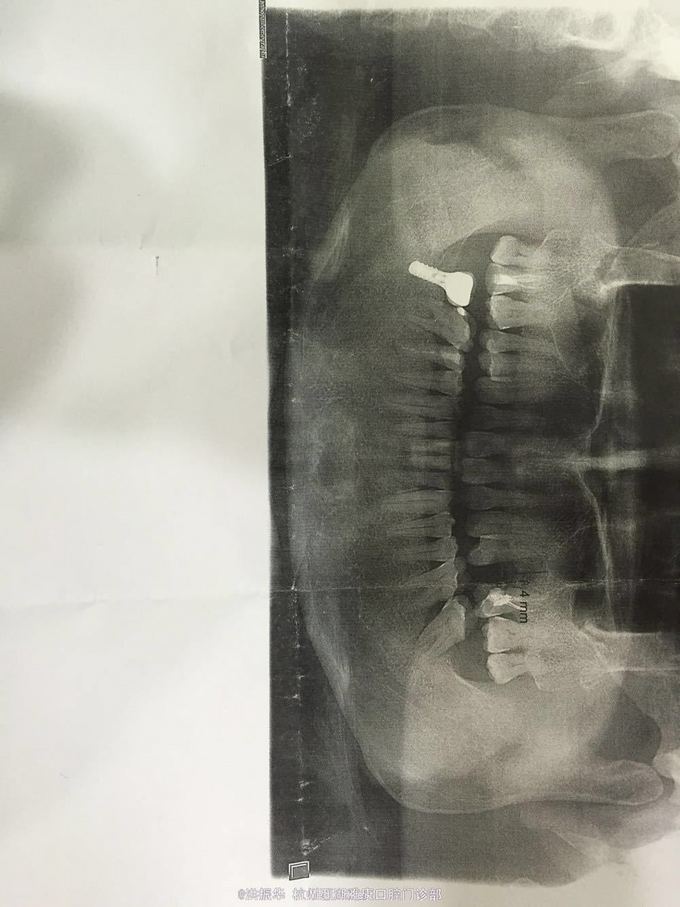

患者某男,69岁,左上后牙缺失,要求种植,伴有高血压史,糖尿病史。